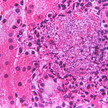

Leibniz-Wirkstoff 2017 Studie: Pilztoxin durchlöchert Zellmembran

Mykosen können lokal oder systemisch auftreten und werden häufig mit dem Hefepilz Candida albicans in Verbindung gebracht. Der Pathomechanismus ist im Einzelnen... Mehr»